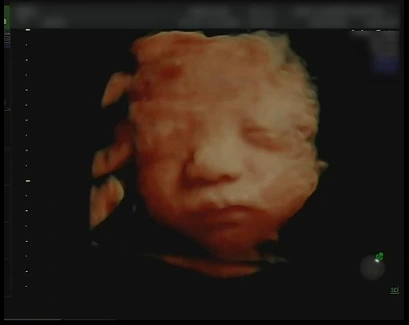

내 아이의 얼굴이 궁금해

인생에는 과업이 왜 이리도 많은지. 결혼이라는 관문을 넘고 나자 주변에서는 임신을 권하기 시작했다. 자연스러운 인생의 수순인 것처럼. 그 자연스러운 강압에 질려 임신에 강력히 저항하던 나는 ‘호르몬’이라는 더 강한 본능 앞에 무릎을 꿇고 말았다. 너무도 당연한 것처럼, 내 아이의 얼굴이 궁금해진 것이다.

그 말이 나에게 깊게 다가왔다. 나는 ‘귀한 일’을 해내고 있구나. 그러느라 이렇게 몸이 힘든 거구나. 그 말을 들은 이후로 나는 좀더 내 몸의 변화를 긍정적으로 받아들일 수 있게 되었다. 기쁜 마음으로 아이를 기다리던 2021년 7월 9일, 드디어 나는 그렇게 궁금하던 아름이의 얼굴을 보게 되었다.